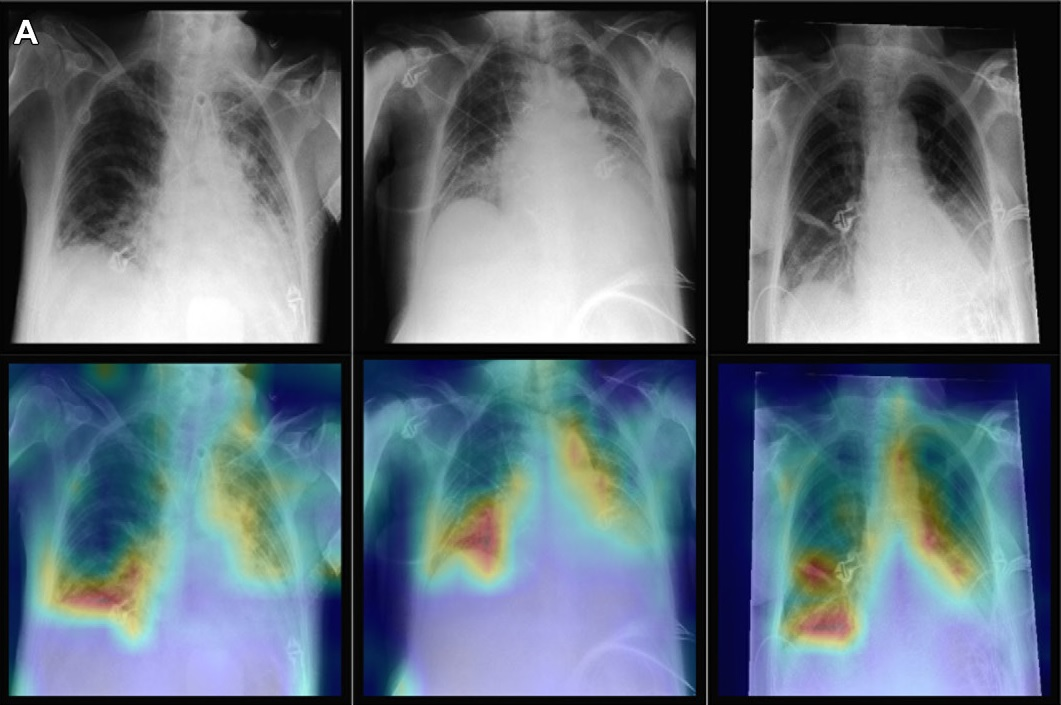

To that end, the researchers specifically analyzed a chest x-ray foundation model based on more than 800,000 chest x-rays from India and the U.S. proposed in an article published July 19, 2022 in Radiology.

The researchers compared the performance of the proprietary foundation model (SupCon, Google Health) with a reference model they built in evaluating 127,118 chest x-rays with associated diagnostic labels. The group inspected the generated features of the proprietary model for the presence of biases that could potentially lead to disparate performance across patient subgroups.

According to the analysis, significant differences were found between male and female and Asian and Black patients in the features related to disease detection.

Specifically, compared with the reference model performance across all subgroups, the foundation model's classification performance on the "no finding" label dropped between 6.8% and 7.8% for female patients, and performance in detecting "pleural effusion" – a buildup of fluid around the lungs – dropped between 10.7% and 11.6% for Black patients, the researchers reported.